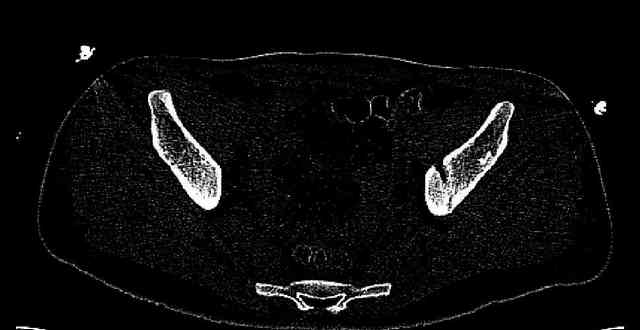

Some more images. Does it help to guess which part of the acetabulum is displaced?